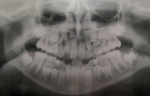

Чтобы отбросить все сомнения, необходимо сразу же сделать снимок челюсти. На нем будут видны зачатки постоянных зубов. Волнуетесь, что они вырастут криво или даже сзади основных? В этом случае необходимо ставить детям брекеты. Можете быть уверены, что данный недостаток полностью устранится.

- Если вы всё-таки волнуетесь, лучше сходить на приём к специалисту. Он с лёгкостью сможет определить, есть ли у малыша адентия. Для этого ему понадобится рентген челюсти ребёнка. К тому же, малышу могут сделать цифровой снимок, который будет менее опасным в плане облучения и более информативным.

Совет: по рентгеновскому снимку врач сможет точно определить, есть ли у ребенка зачатки коренных зубов, как они расположены, и назвать примерную дату их прорезывания. Рентгенография помогает выявить патологии на ранней стадии, а это значит, вы получаете больше шансов успешно и быстро исправить проблему. Потому, если врач рекомендует рентген – не отказывайтесь.

Без клинического осмотра и оценки рентгеновского снимка судить невозможно. Совершенно не исключено, что он уже на подходе, но все, же рекомендуем сделать рентгеновский снимок, который называется ортопантомограмма, и обратиться к стоматологу-ортодонту.

Необходим осмотр и рентгеновское исследование ортопантомограмма (панорамный снимок челюстей), на котором будет видно зачатки постоянных зубов и степень их сформированности. После можно сказать о примерных сроках их прорезывания. В среднем, центральные резцы прорезываются в 6-7 лет. Проконсультируйтесь очно с детским врачом-стоматологом.

Необходимо провести рентгенологическое обследование ортопантомограмма (панорамный рентгеновский снимок зубов и челюстей). На ней будут видны все зачатки постоянных зубов и стадию их формирования. Верхние постоянные резцы в среднем, прорезываются в возрасте 7-8 лет. Проконсультируйтесь очно с детским врачом-стоматологом.